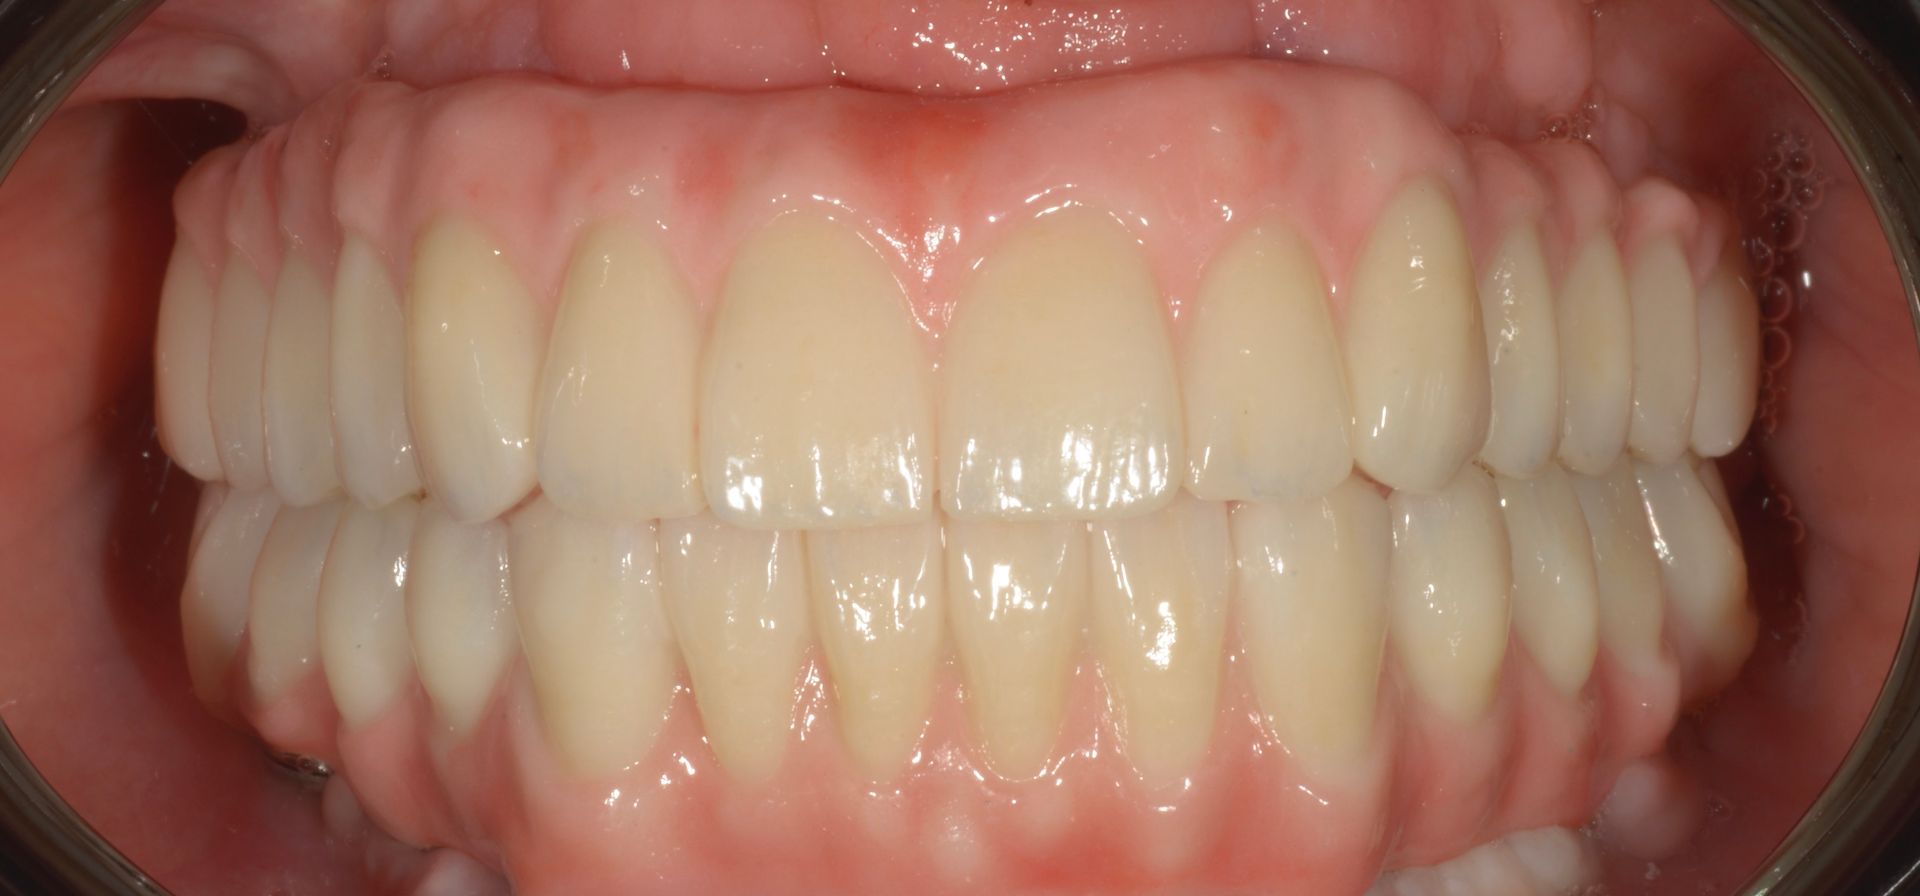

Il paziente era molto amareggiato perché non tollerava la protesi totale e aveva dolori dovuti agli impianti infetti dell'arcata inferiore. Dopo un attento studio del caso, in cui sono state studiate le forme e le altezze delle nuove protesi e abbiamo eseguito una pianificazione digitale dell'intervento chirurgico impiantare abbiamo inserito 5 impianti nel superiore con una rigenerativa orizzontale e 4 impianti nell'inferiore. a distanza di 4 ore dall'intervento abbiamo caricato gli impianti con le protesi provvisorie a carico immediato fatte con resina e una struttura in titanio, a distanza di 6 mesi sono state sostituite con 2 arcate titanio zirconio.